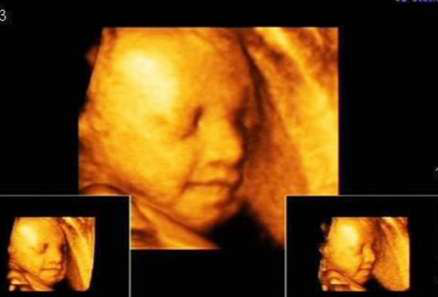

三维彩超就是通过容积数据重建的一个宝宝的颜面部的轮廓,你也可以把他(她)想象成一个捏出来的泥娃娃一样,看得到表面的样子轮廓,但是颜色是单一的,画面是静止的。

而四维彩超,也叫实时三维,是在三维彩超的基础上加了时间轴,通俗点讲,就是把三维的图像录成一个小视频了,如果你足够幸运,你将有机会看到你的宝宝在笑、打豁嗨、吃手指妹儿等等一系列的萌动作哟。

由此看来,这三种检查不能简单的说哪一种更好,他们各有所长,至于具体选择哪一种就要根据你的需求来决定。

不论是三维还是四维,都是合成的一张相给准妈妈、准爸爸看的,根本的根本是你首先要弄清楚,你们做的是不是胎儿系统超声检查,也就是Ⅲ级筛查,这个才是针对胎儿器官结构的系统大排畸!如果你只想单纯的给肚子里面的小宝宝拍个照片什么的,那三维四维是OK的!